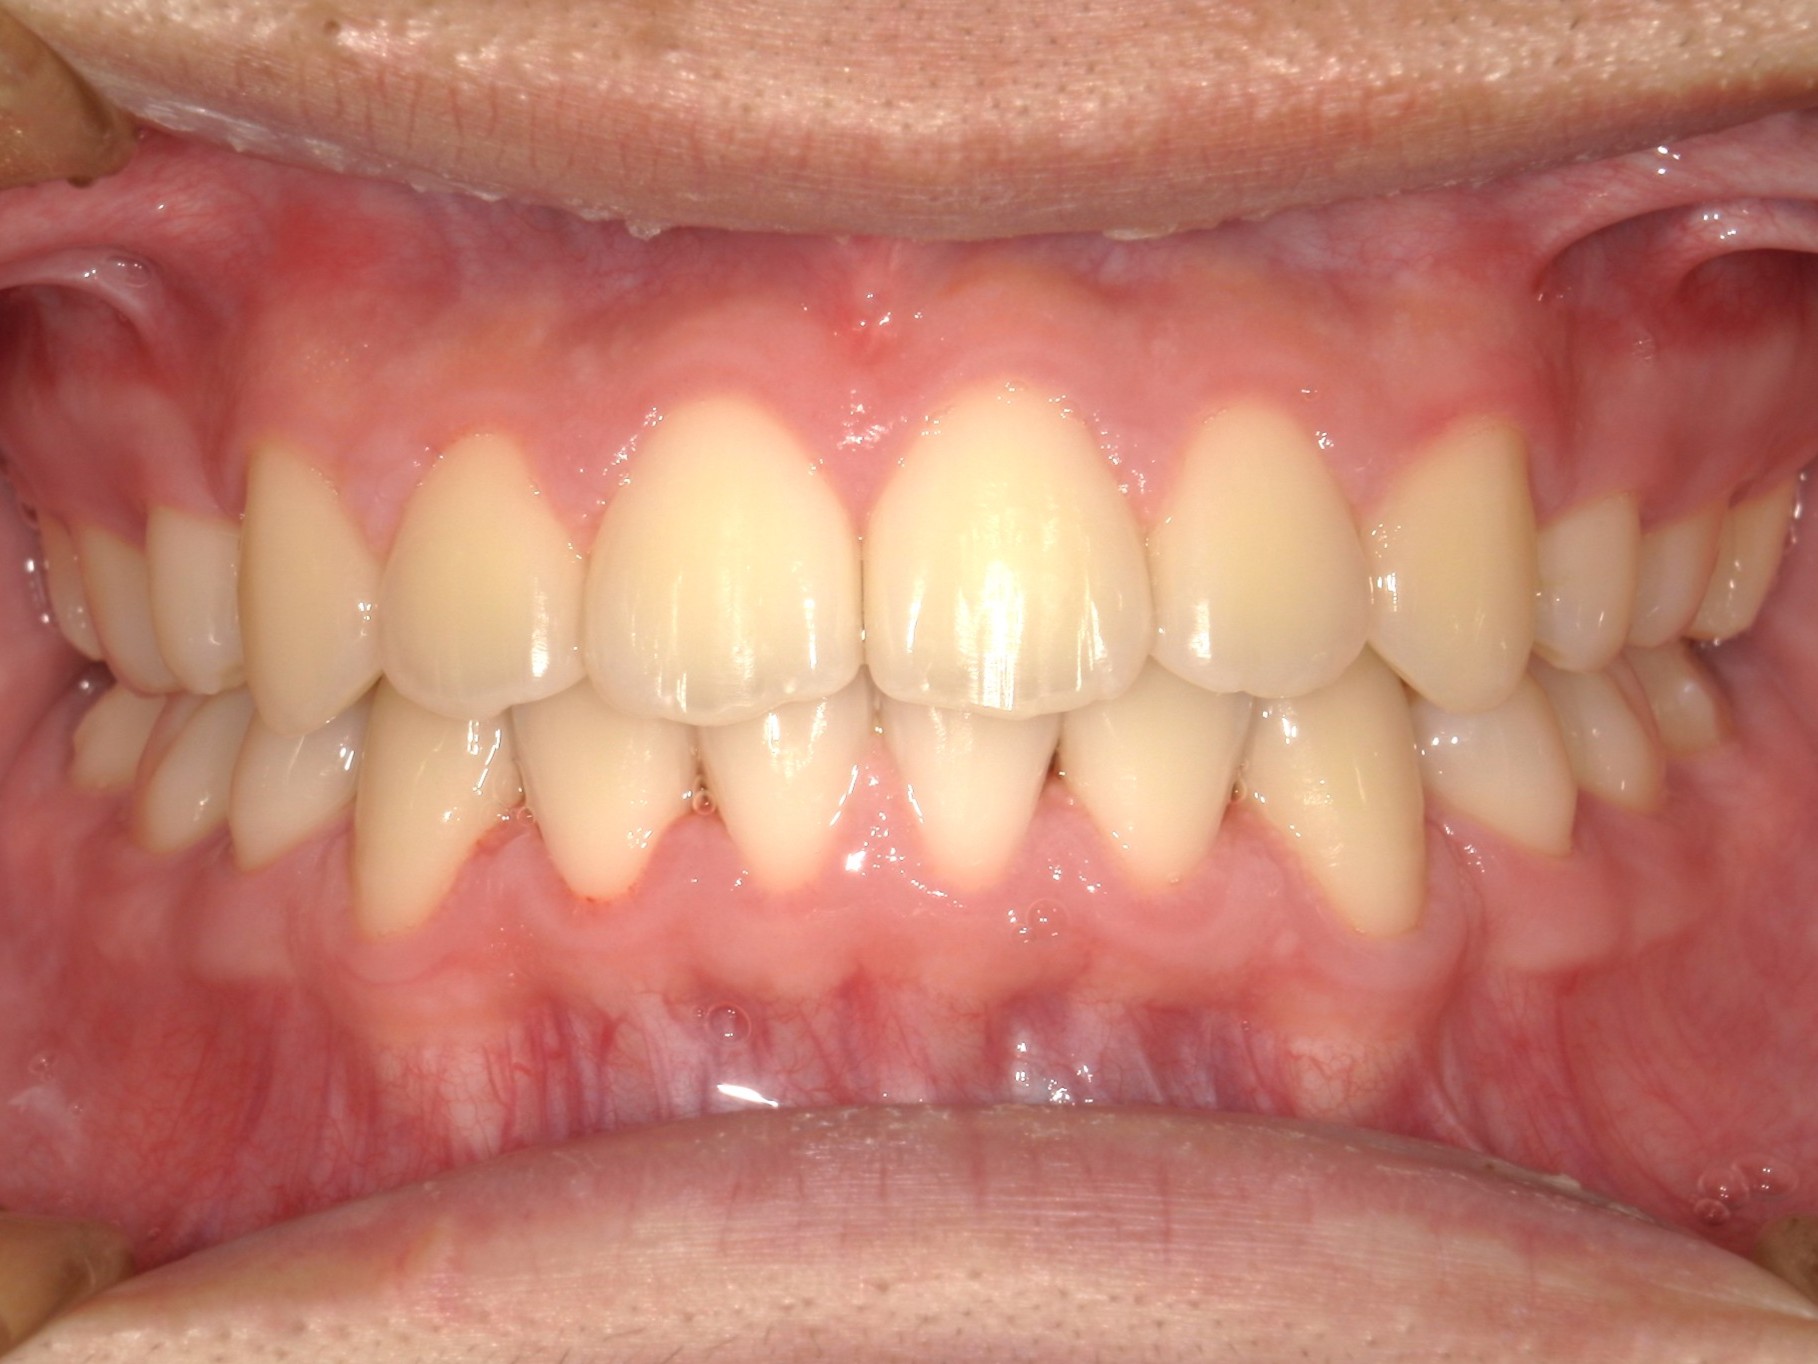

口内正面

治療前

治療後

上の前歯の前突と上下顎歯列のがたつきを認めました。

上の歯を後方へ移動させるスペースと、上下の歯のがたつきを改善するため、上下の歯をそれぞれ2本ずつ抜きました。

治療の仕上げの段階では顎間ゴムを使用して上下の歯が緊密に噛み合うようにしました。

結果、上の前歯の前突感と上下の歯列のがたつきが改善し、審美性も良好に仕上げることが出来ました。